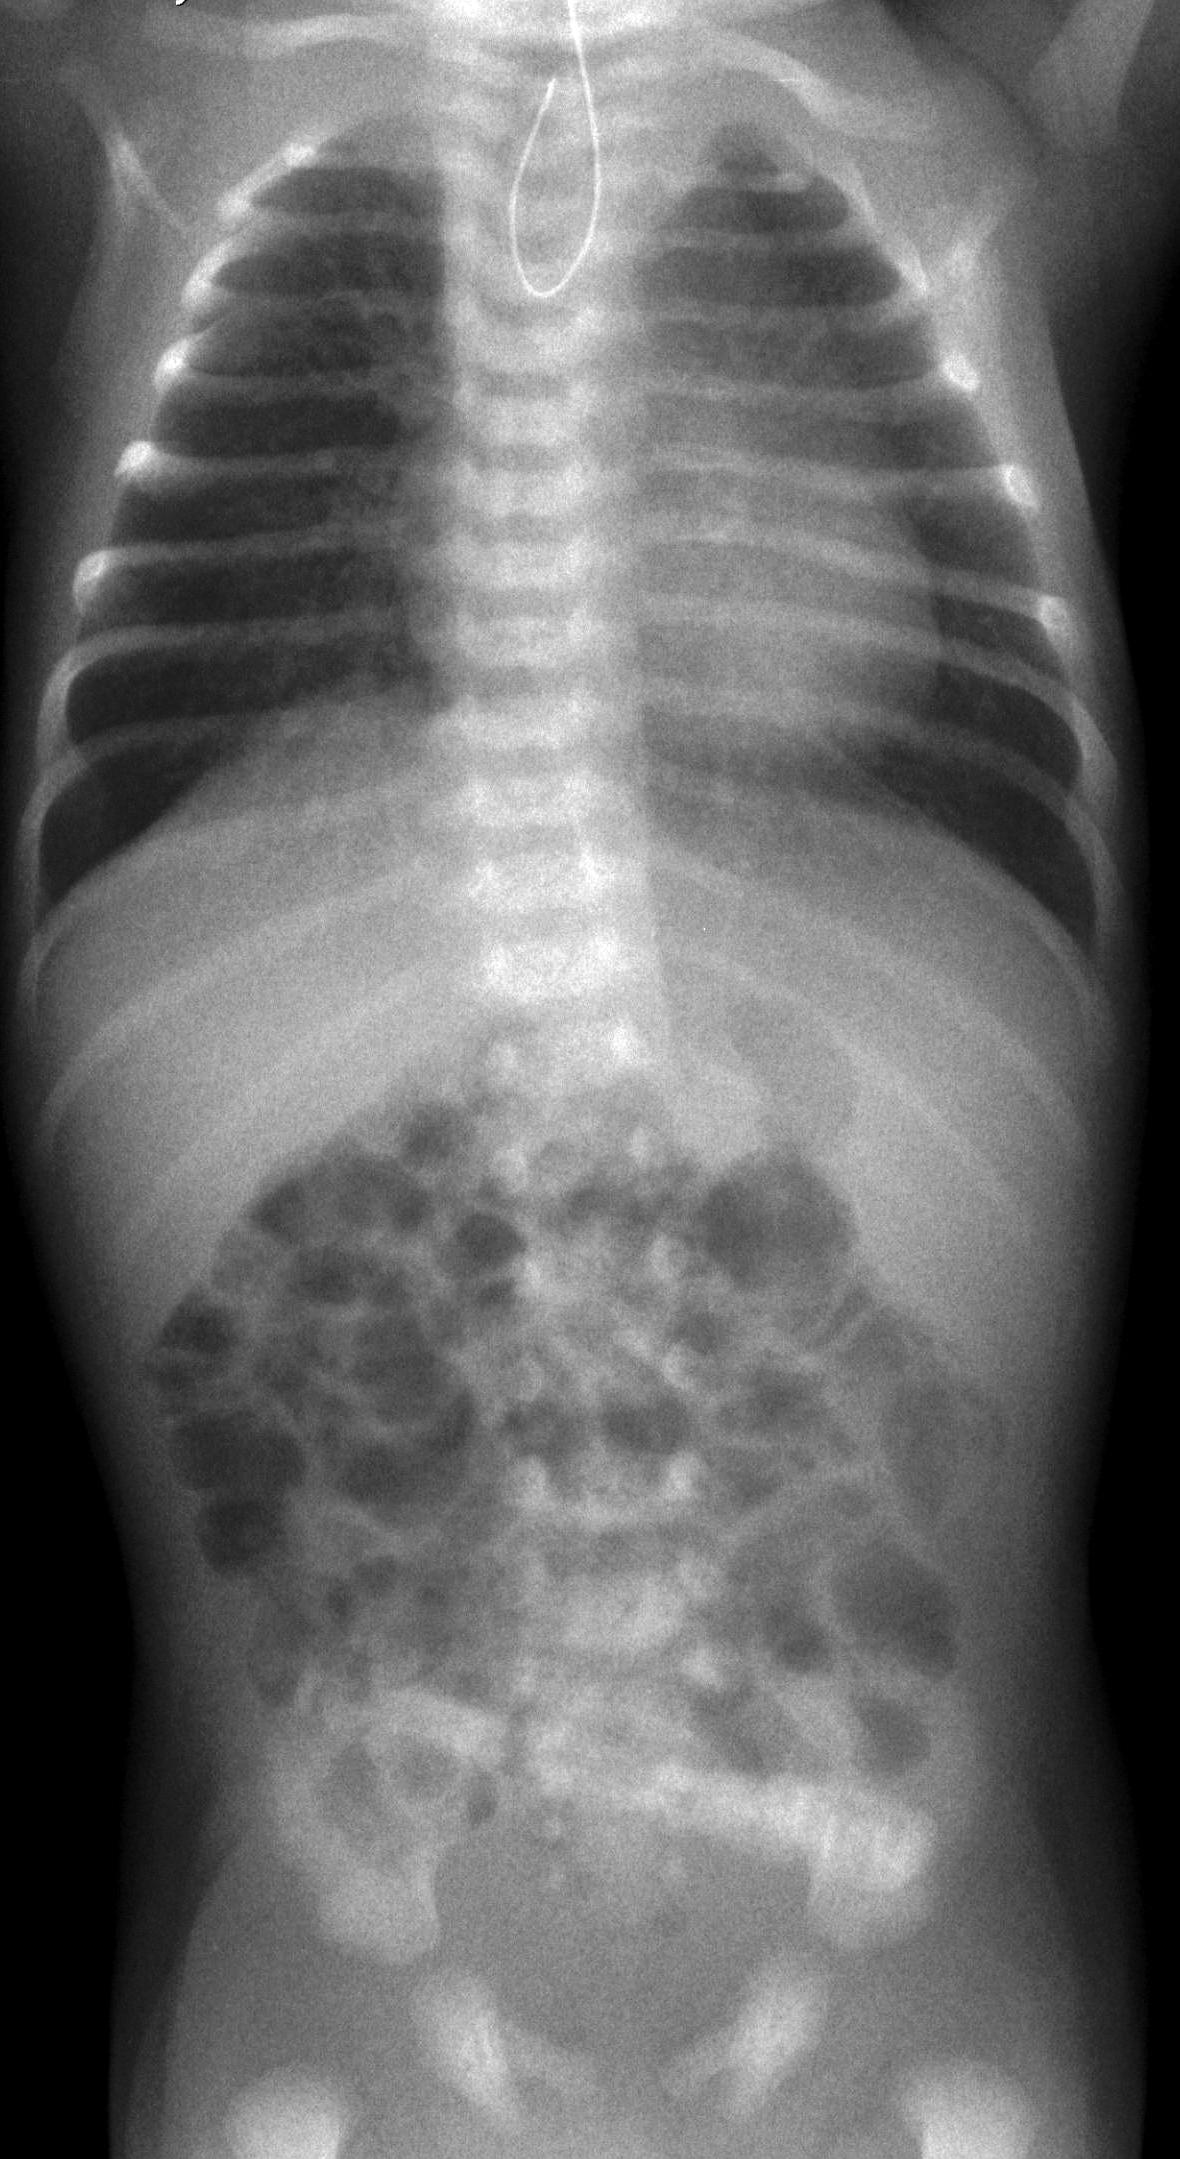

Necrotizing enterocolitis (NEC). It is a severe intestinal necrotizing disease of the newborns. It usually occurs as early as the first 10 days of life, but can happen in the first few months after birth. Vomiting, distended intestines, bloody stool, acidosis, peritonitis and perforation are frequent findings. Plain abdominal X-ray can be non-informative in the early stages of the disease; later distension indicates the separation of loops due to wall thickening. Often, air bubbles appear in the intestinal subserosal or submocosal layers, as characteristic signs of “intestinal pneumatosis”. The intramural air can diffuse to the mesenteric veins and appear in the portal circulation in the projection of the liver. Free abdominal air is indicative of perforation and requires surgical intervention. US examination can reveal these characteristics of the disease before X-ray is indicative. US can depict thickened intestinal wall, portal and intramural air, abdominal free fluid or abscesses.

19. Distended bowel loops. Air is seen in the intestinal wall, intestinal pneumatosis. Necrotizing enterocolitis.